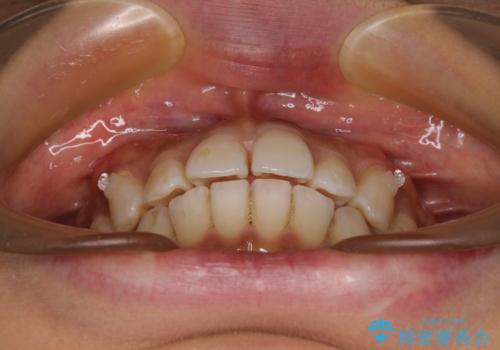

- 全体的な歯列の叢生を気にして来院された患者様です。

奥歯の咬み合わせを見ると、片方は上顎が下顎に対して相対的に前方にある状態でした。

咬み合わせを改善するためには、上顎臼歯を後方に移動させた咬み合わせにする必要があります。

インビザライン単体で改善することも可能ですが、ディープバイトのためインビザライン単体で達成する可能性が低いと考えられたため、カリエール・ディスタライザーという補助装置を併用して、より確実性を上げることとしました。

奥歯の咬み合わせ改善後に、インビザラインにて歯列を整えることとしました。

カリエールディスタライザーを併用したことで、確実かつ短期間で治療を終えることができました。